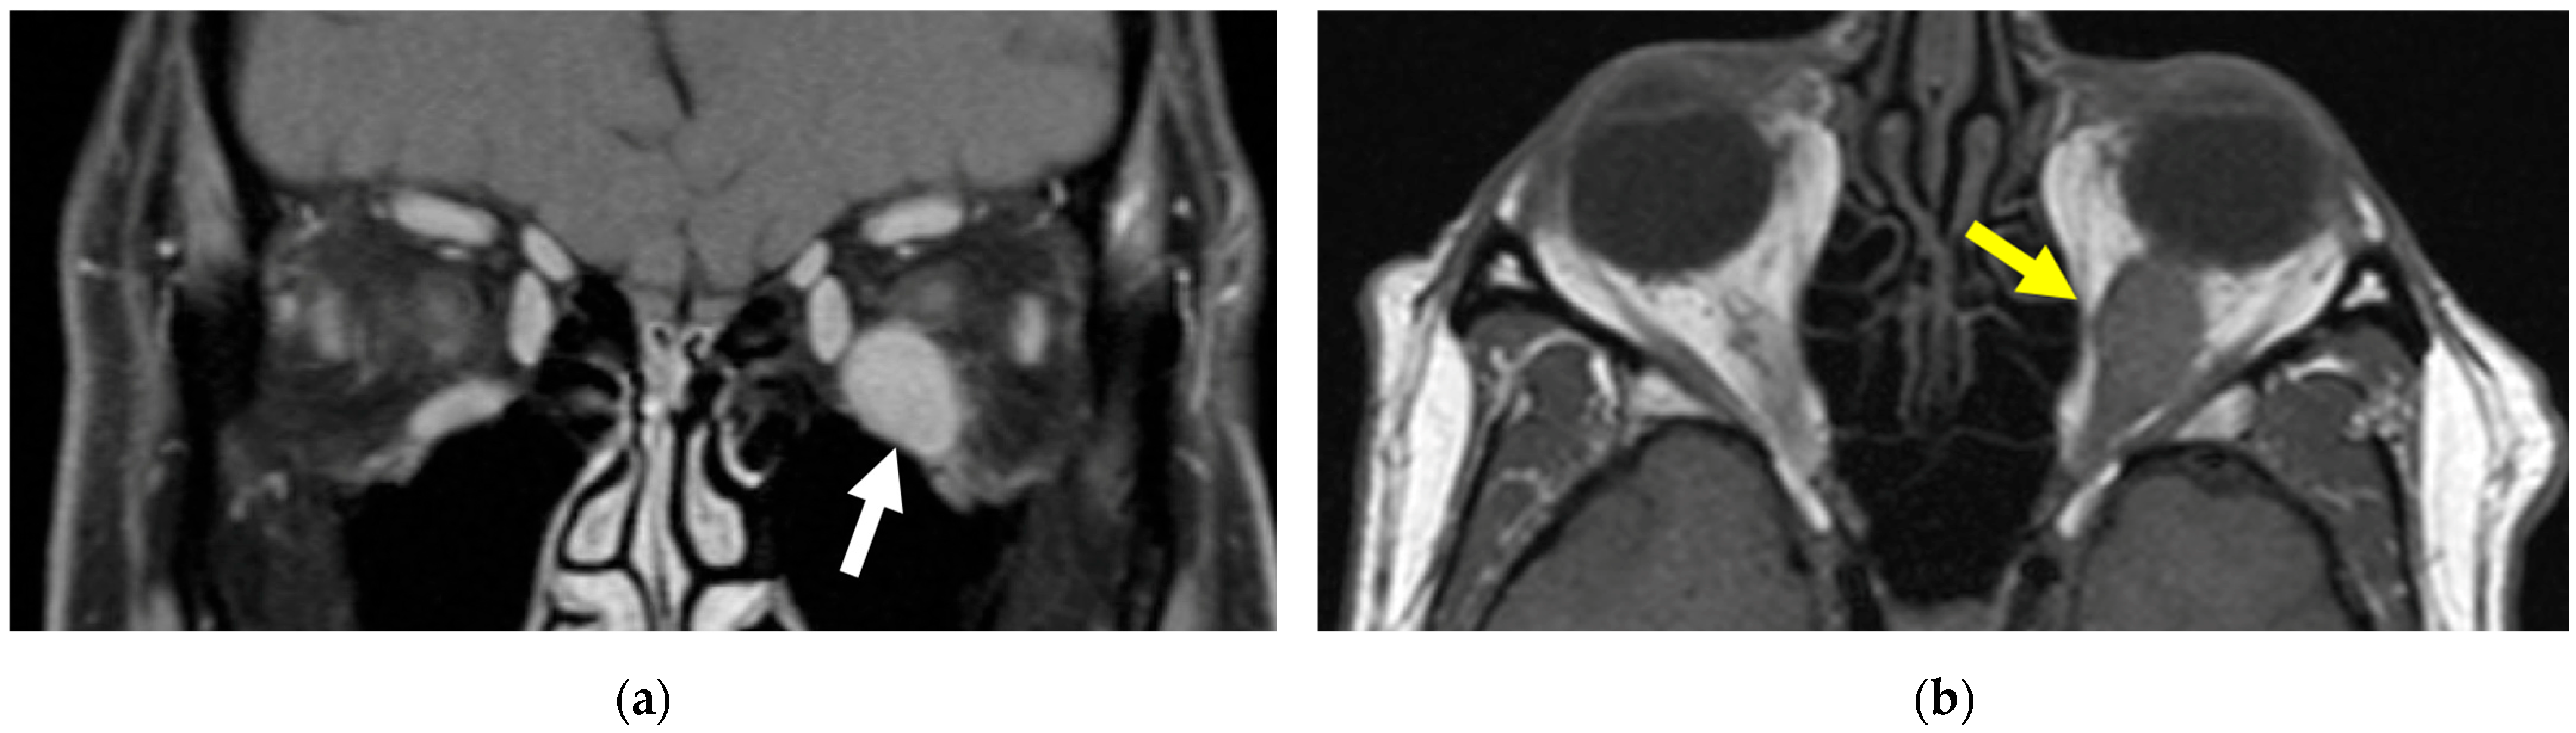

2. Case Presentation